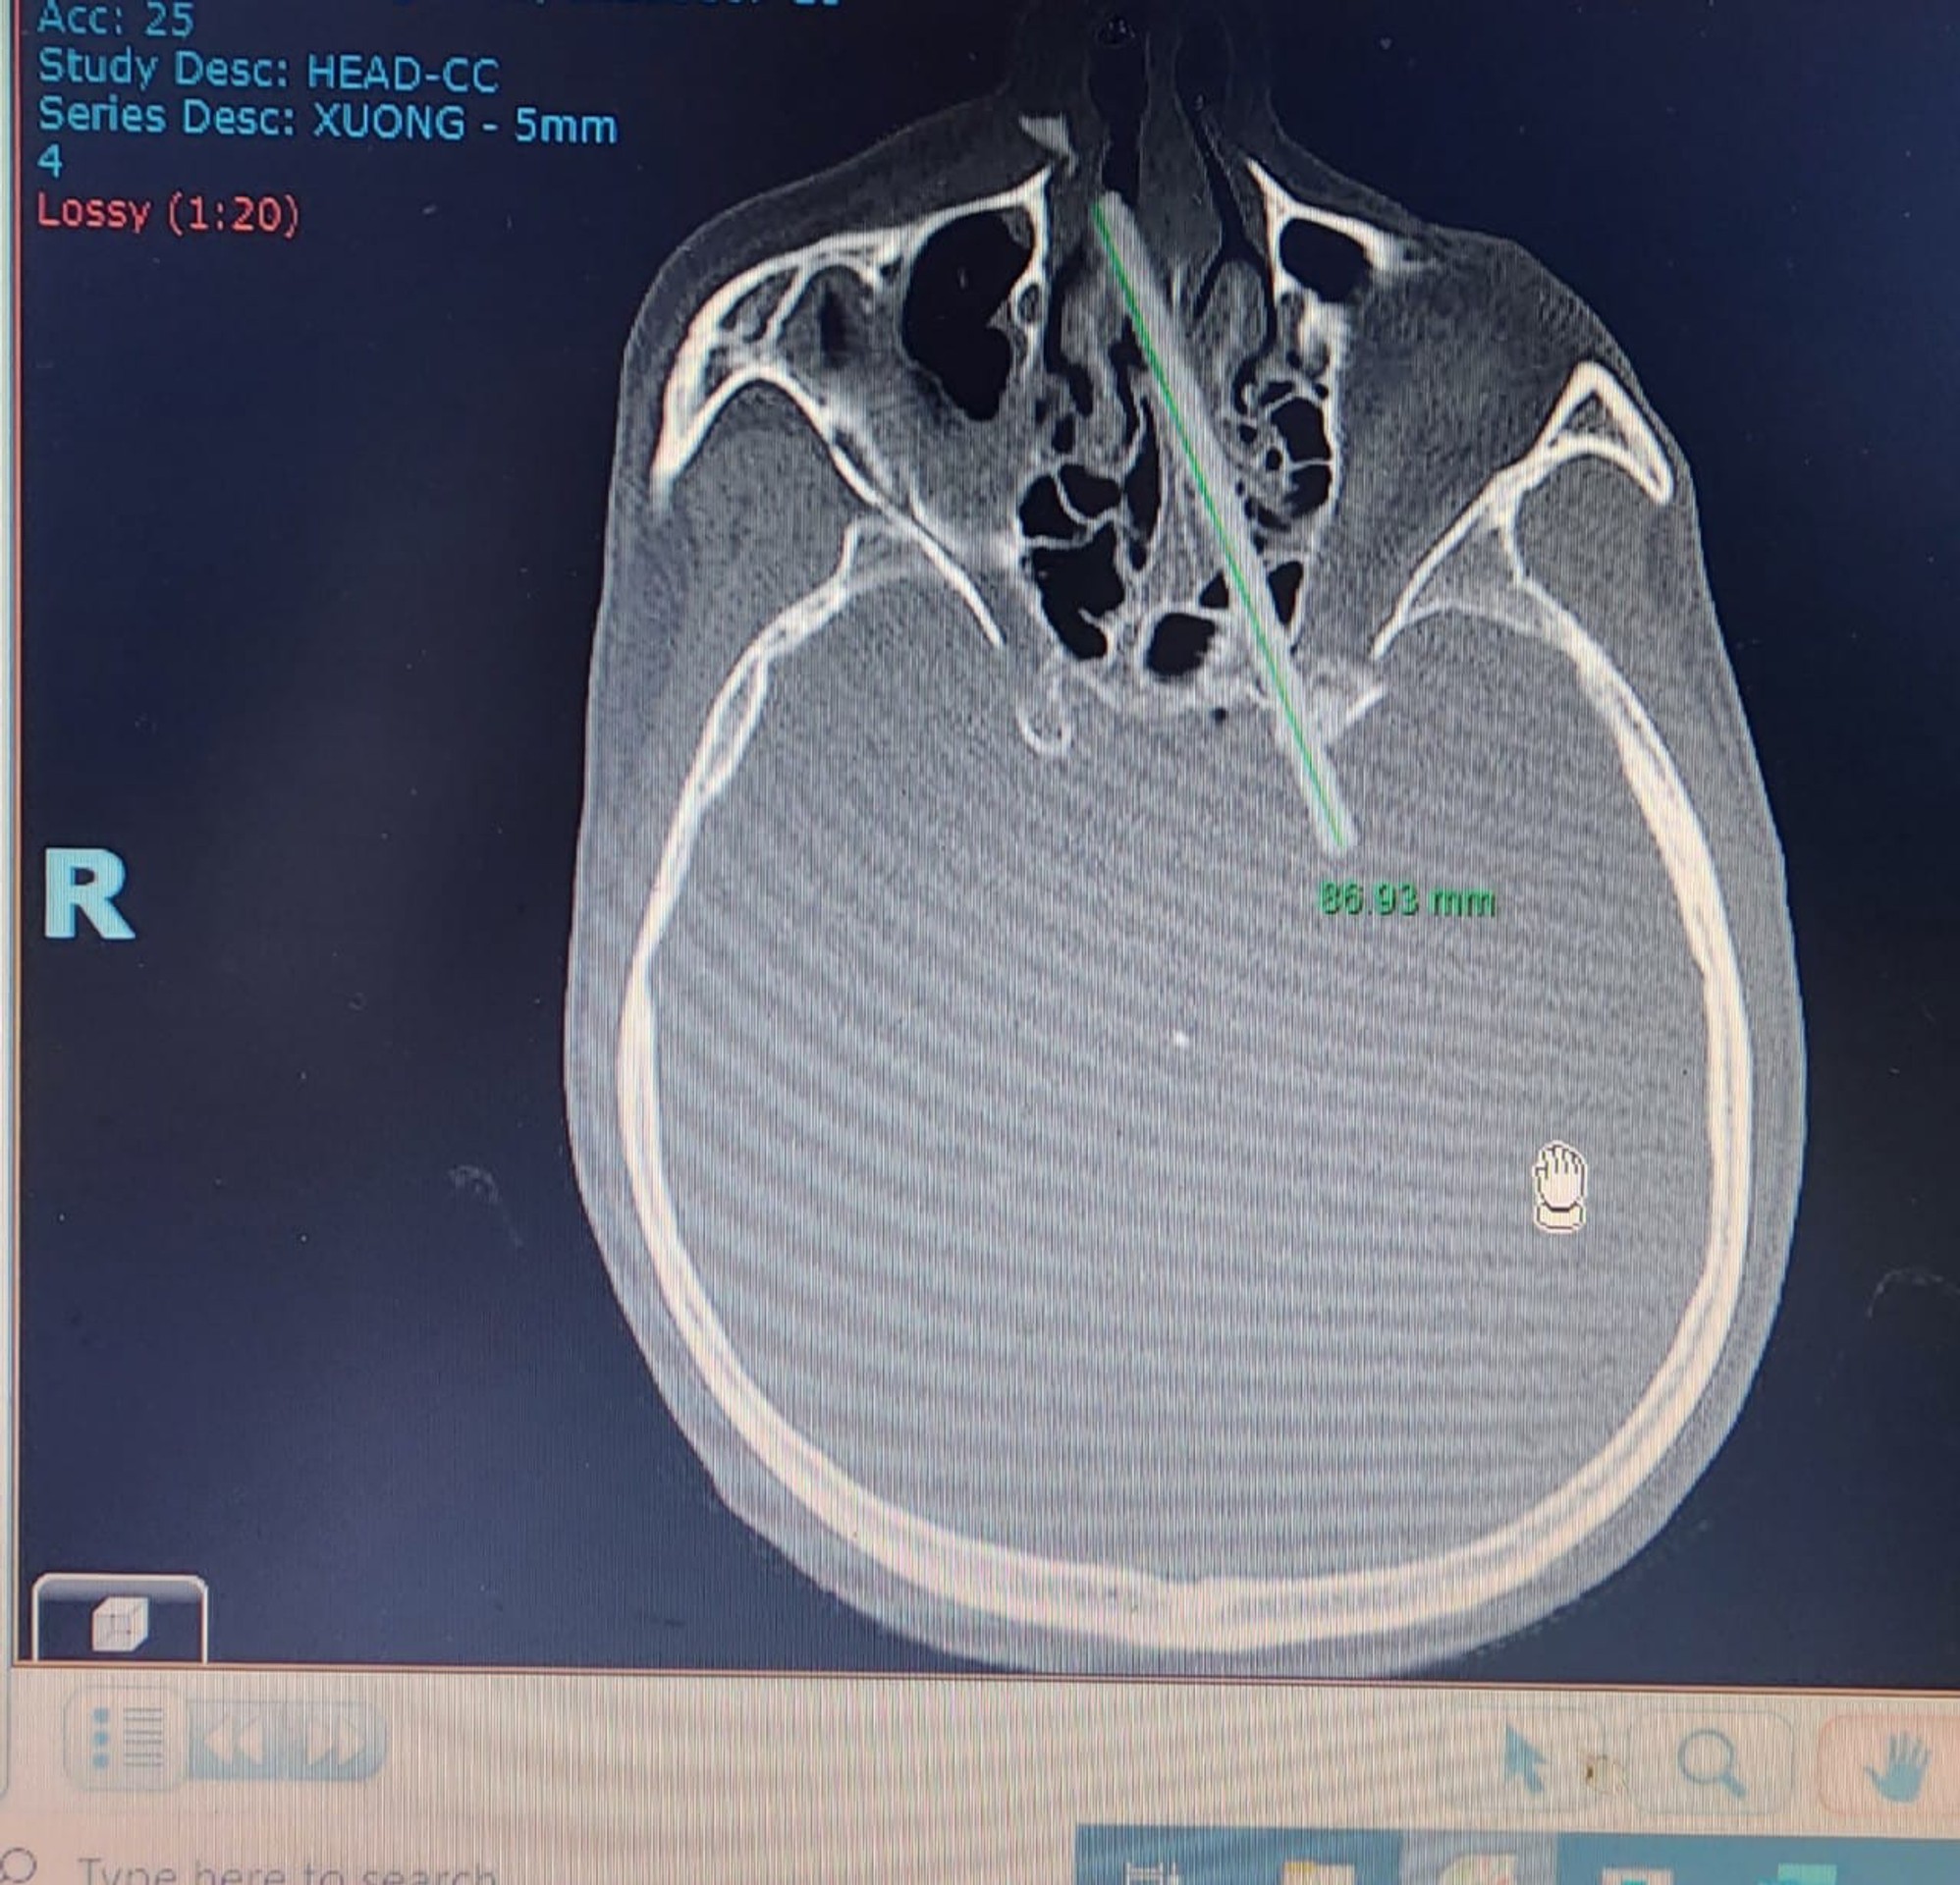

Röntgenová snímka lebky.

Zdroj: Vietnam-Cuba Friendship Hospital